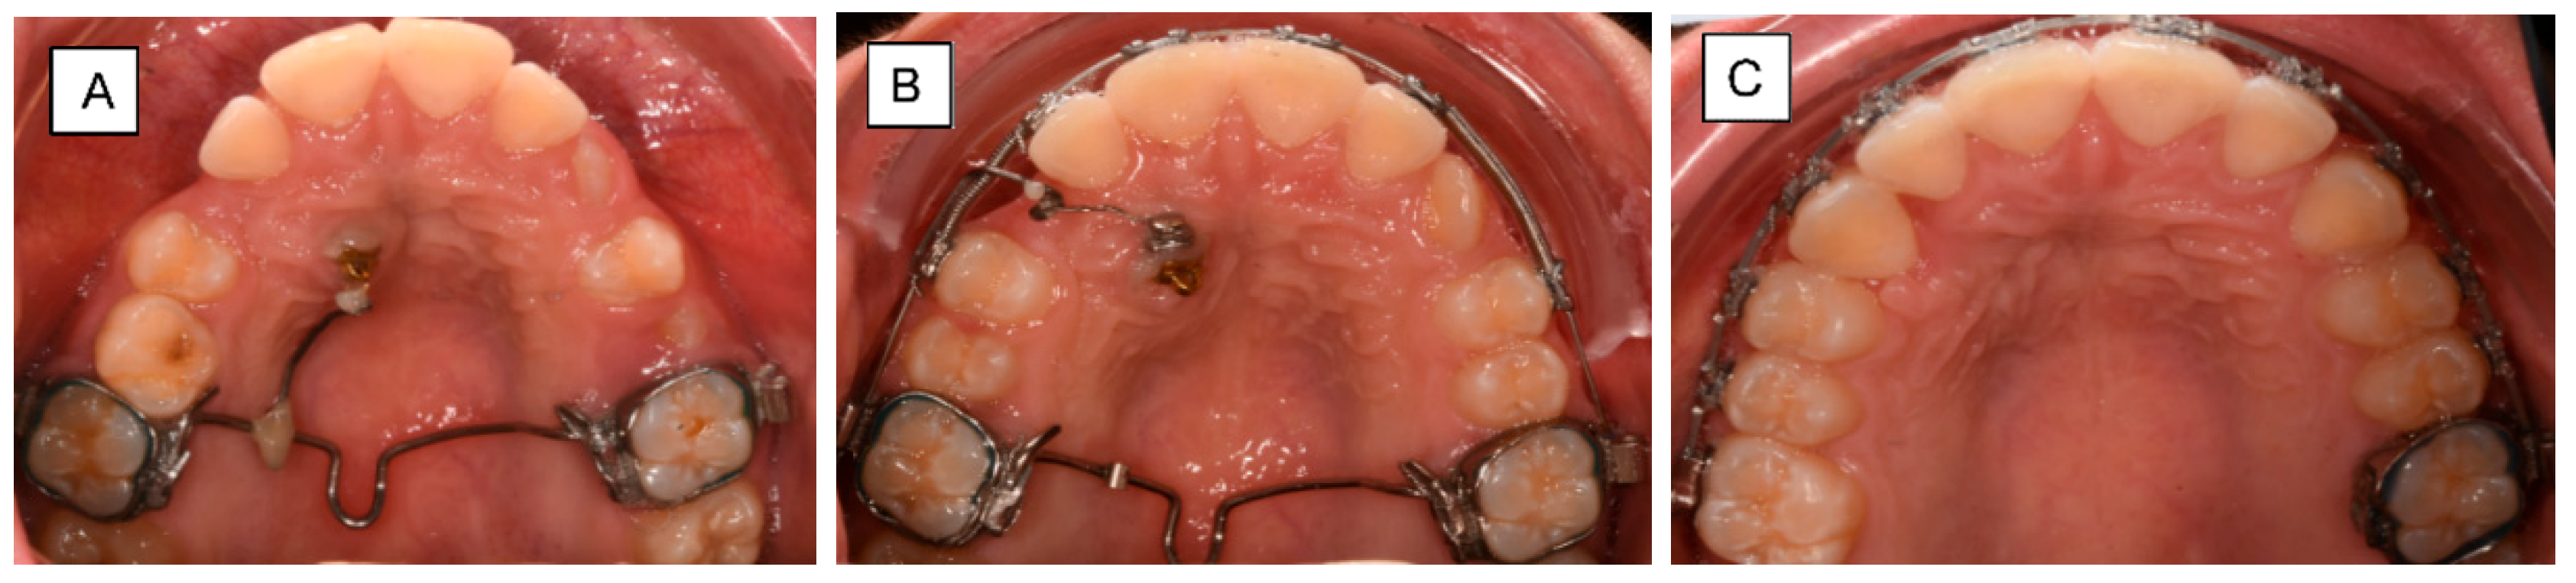

3.2. Palatal Impaction